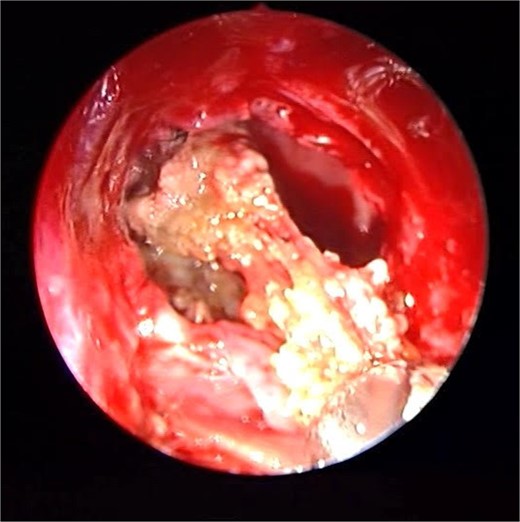

Patient presented to the emergency department with four days history of sever left side headache associated with nausea and vomiting, and nasal discharge with on\off nasal obstruction. Two days history of diplopia with lateral gaze of the left eye, with decrease the visual acuity. Ophthalmologic examination revealed left abducens nerve palsy. Other neurologic examinations were within normal. Endoscopic nasal examination revealed left multiple grade two nasal polyps occupying the middle meatus. Pre-operative brain computed tomography (CT) shows bilateral near total opacification and expansion of the paranasal sinuses and nasal cavity (Fig. 1). Additionally, there is evidence of invasion of the left cavernous sinus with encasement of cavernous segment of left internal carotid artery (ICA). Furthermore, pituitary gland and optic chiasm displaced superiorly. Magnetic resonance imaging revealed that the sphenoid sinus is expanded and bulging superiorly into the pituitary fossa causing displacement of pituitary gland and stalk without mass effect upon the optic chiasm (Fig. 2). It extends laterally causing effacement of the cavernous sinus and left Meckel’s cave. No evidence of intracranial extension. The patient underwent functional endoscopic sinus surgery with computer-assisted navigation system. Intraoperatively, sphenoid sinus was full of fungal mud and mucin (Fig. 3). The polyps were removed completely from the nasal cavities, fungal mud, and mucin were removed from the sinuses (Figs 4 and 5). Patient had dramatic improvement after surgery, the rhinosinusitis symptoms are resolved, the diplopia has been improved, and the paranasal sinuses were clear. The patient was discharged with topical corticosteroid and saline irrigations.

Endoscopic intraoperative image of the sphenoid sinus post removal of the fungal mud and mucin from the lateral wall of the sphenoid sinus.